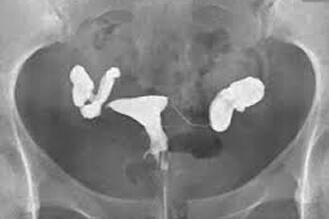

bilateral fallopian tubes swollen and blocked

To examine if bilateral fallopian tubes are patent, swollen or blocked.

After a vaginal speculum is inserted to spread and hold open your vaginal walls, a syringe held at your cervical region will be used to inject a contrast medium into your uterus. If both of the fallopian tubes are patent, the contrast medium will flow from the uterus to bilateral fallopian tubes and further into the pelvic cavity. With the use of fluoroscopy, we may capture whether the contrast medium flows into the pelvic cavity. The entire examination will take approximately 10 minutes.